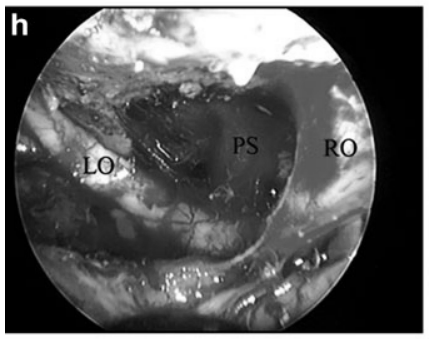

h 内镜下全切后所见:左视神经(LO)、右视神经(RO)及垂体柄(PS)均保持完整。